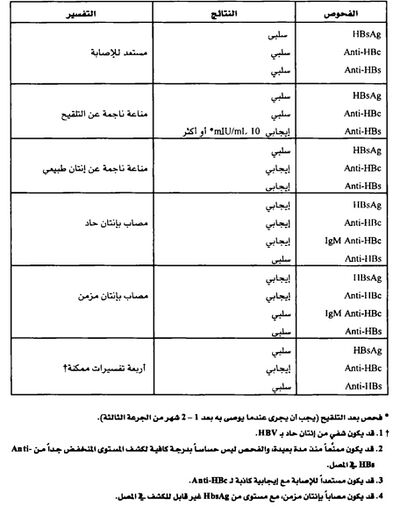

إن إظهار مستضدات أو أضداد نوعية أو كليهما في المصل يثبت التشخيص. وقد تم تمييز ثلاثة نظم مستضدية ـ ضدية لالتهاب الكبد ب مفيدة سريرياً هي:

1- المستضد السطحي لالتهاب الكبد ب (HBsAg) وضده (anti-HBs).

2- المستضد اللبي لالتهاب الكبد ب (HBcAg) وضده (anti-HBc).

3- المستضد هـ لالتهاب الكبد ب (HBeAg) وضده (anti-HBe).

وتتوافر عتائد تجارية لجميع الواسمات الڤيروسية ما عدا المستضد اللبي (HBcAg). ويمكن اكتشاف المستضد السطحي (HBsAg) في المصل مدة تتراوح ما بين عدة أسابيع قبل بدء الأعراض وبين عدة أيام أو أسابيع أو أشهر بعد بدئها؛ ويوجد في المصل أثناء العداوي الحادة ويستمر وجوده في العداوى المزمنة. ويدل وجود المستضد السطحي لالتهاب الكبد ب إلي عداوئية الشخص. ويظهر ضد المستضد اللبي anti-HBc عند بدء المرض ويستمر مدة غير محدودة. ولذلك يدل إظهار ضد المستضد اللبي في المصل على وجود عدوى بڤيروس التهاب الكبد ب حالية أو سابقة؛ ويوجد الأيج م IgM المضاد للمستضد اللبي بعيار مرتفع أثناء العدوى الحادة، ويختفي عادة خلال 6 أشهر ولكن قد يستمر في بعض حالات التهاب الكبد المزمن. وهذا الاختبار قد يشخص العدوى الحادة بڤيروس التهاب الكبد ب تشخيصاً يعول عليه. ويرتبط وجود المستضد هـ لالتهاب الكبد ب بالارتفاع النسبي في القدرة على الإعداء.

يعتبر فحص المستضد السطحي HBsAg هو الفحص الأكثر استعمالاً لتشخيص الإنتانات الحادة بڤيروس HBV وكشف الحملة. حيث يمكن كشفه باكراً منذ الأسبوع الأول أو الثاني وحتى الأسبوع 11- 12 من التعرض لڤيروس HBV، وذلك إذا استخدمت طرق مقايسة حساسة. يدل وجود HBsAg على أن الشخص معدٍ بغض النظر عن كون الإنتان حاداً أو مزمناً.

تتطور الأضداد اللبية Anti - HBc في كل إنتانات HBV، وهي تظهر بعد HBsAg بفترة قصيرة في المرض الحاد، و تدل على الإنتان بڤيروس HBV في وقت سابق غير محدد. تتطور هذه الأضداد بعد الإنتان بڤيروس HBV فقط، أي لا تتطور عند الأشخاص الذين لديهم مناعة لڤيروس HBV ناجمة عن التلقيح. تستمر الأضداد اللبية Anti - HBc بشكل عام مدى الحياة، وهي ليست واصمة مصلية للإنتان الحاد.

تظهر الأضداد اللبية من نوع IgM Anti - HBc) IgM) عند الأشخاص المصابين بمرض حاد عند بداية المرض تقريباً، وهي تشير لإنتان حديث بڤيروس HBV. تكون IgM Anti - HBc قابلة للكشف بصورة عامة بعد 4 - 6 أشهر من بداية المرض، وتعتبر الواصمة المصلية المفضلة للإنتان الحاد بڤيروس HBV. إن سلبية هذه الأضداد مع إيجابية فحص HBsAg في عينة دم واحدة يشير للانتان المزمن بڤيروس HBV.

إن HBeAg واصمة مفيدة، وتترافق بقوة مع عدد جزيئات HBV المعدية في المصل مع خطورة عالية لنقل العدوى (الإخماج).

أما الضد السطحي Anti - HBs فهو ضد مدل محصن، ويشير وجوده بعد الإنتان الحاد عموماً إلى الشفاء والمناعة ضد عودة الخمج. ويمكن أن يكتسب Anti - HBs ايضاً كاستجابة مناعية للقاح التهاب الكبد B أو نقل بشكل منفعل باستعمال الغلوبولين المناعي لالتهاب الكبد HBIG) B). يعتبر وجود 10 وحدات من الضد السطحي على الأقل دليلاً على المناعة، وذلك باستخدام المقايسة المناعية الشعاعية radioimmunoassay) RIA). أما عند استخدام المقايسة المناعية الإنزيمية enzyme immunoassay) EIA)، فإن الإيجابية الموصى بها من الشركة المصنعة يجب أن تعتبر قياساً مناسباً للمناعة. يمكن أن يعبر عن الضد السطحي Anti - HBs أيضاً بالميلي وحدة دولية / ميلي لتر mIU / mL. ويعتبر مستوى 10 mIU / mL دليلاً على مستوى مناعي محصن.